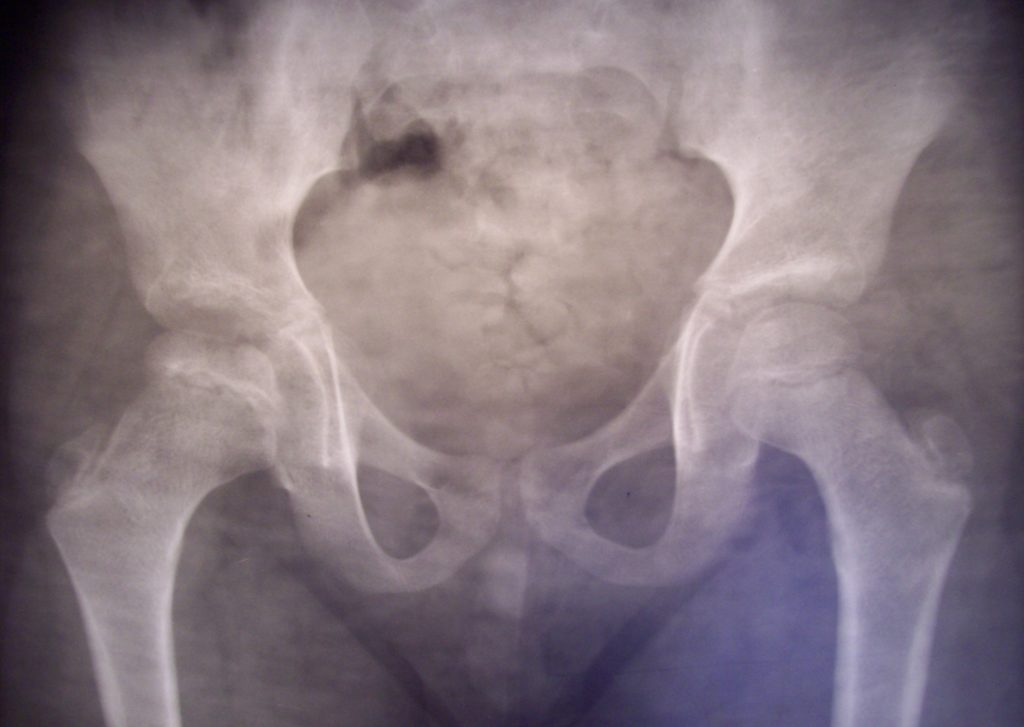

Рентгенограмма пациента К. 9 месяцев, диагноз: Эпифизарная дисплазия правого тазобедренного сустава.